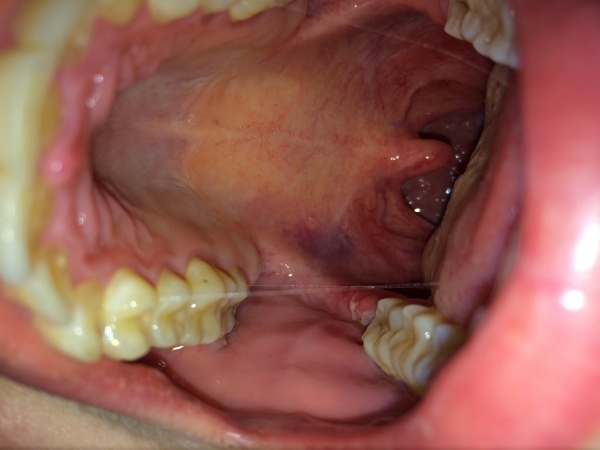

Вчера удалили зуб мудрости на правой стороне внизу, зацепили щеку, сильная боль, было сильно больно глотать, правая сторона горла. Думала, все пройдёт сегодня, но начался гной, глотать все также очень больно. Посмотрела горло, а там на небе синяк образовался.

Что мне делать? Помогите, пожалуйста. Уже щека, чувствую, распухла немного, как будто что-то мешается.